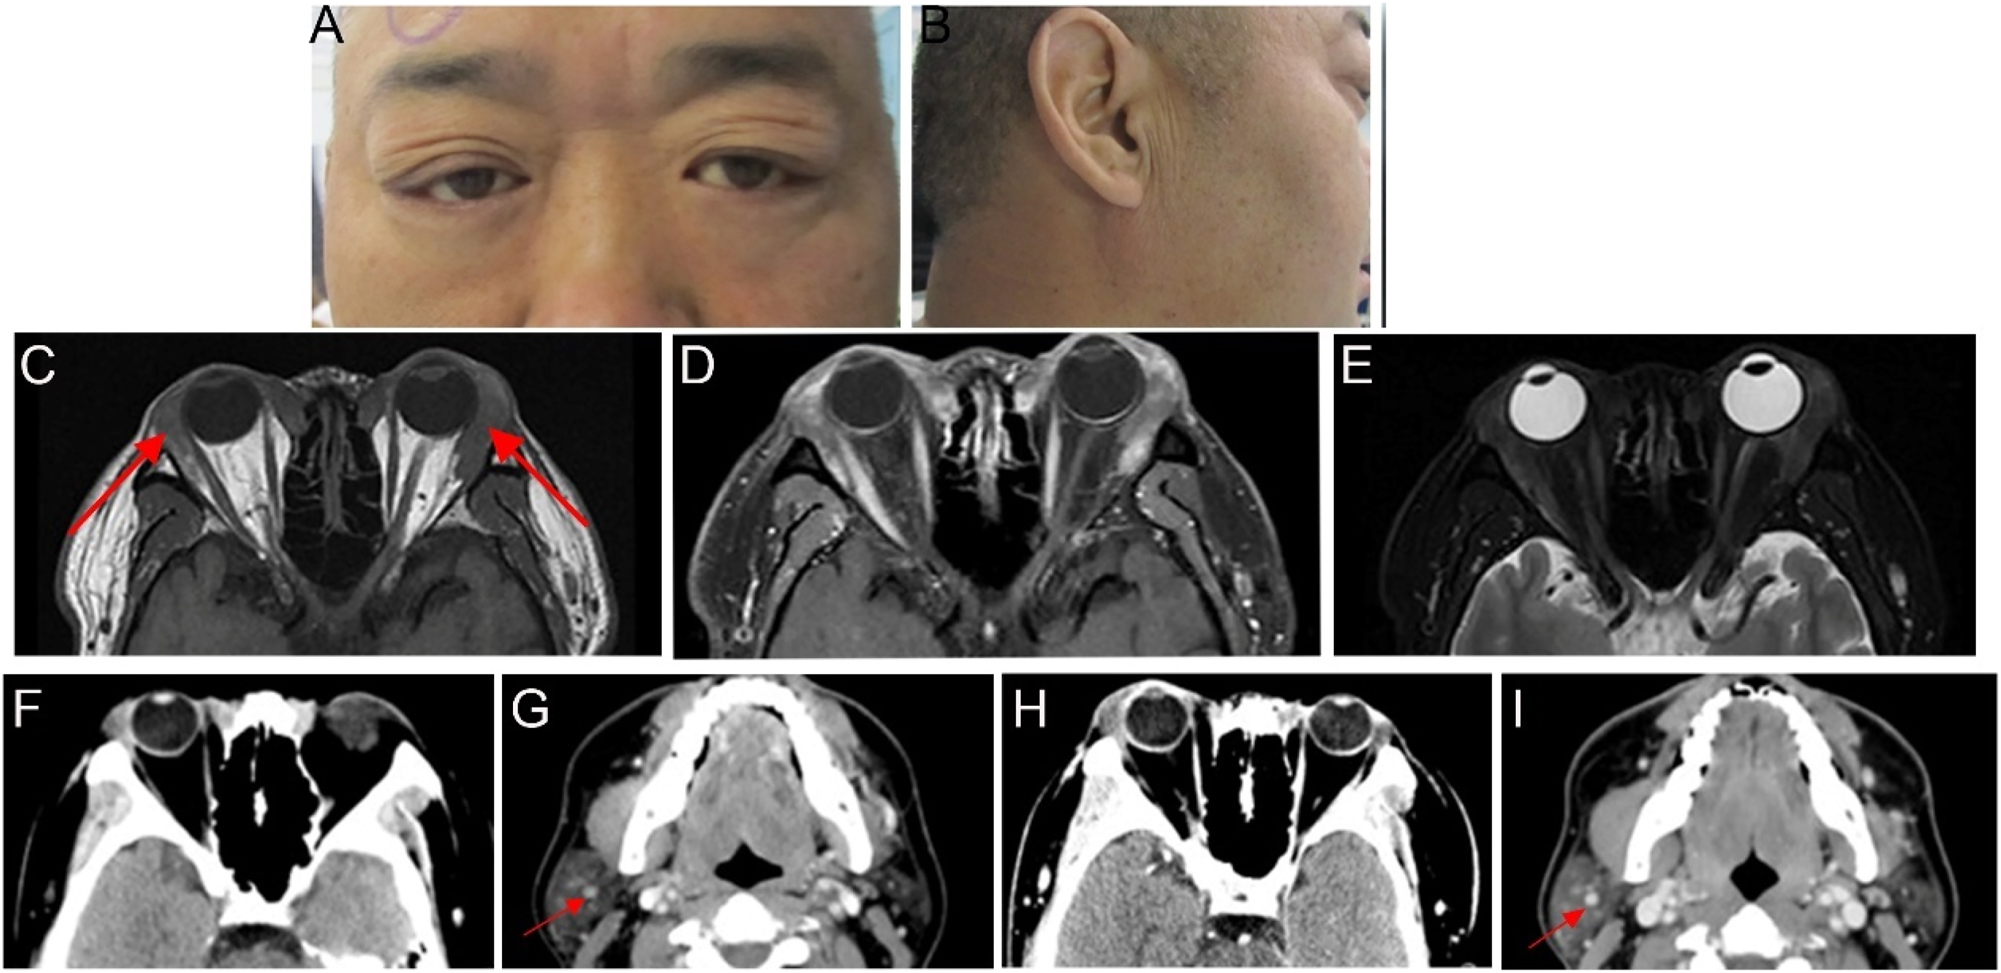

A 48-year-old man presented with bilateral upper-eyelid swelling for 2 years which was accompanied by occasional lacrimation. The medical history of the patient included chronic viral hepatitis C. Six months earlier, he had undergone surgery at another hospital, where his pathological diagnosis was confirmed as amyloidosis. Ophthalmologic examination revealed a visual acuity of 20/20. The swelling was observed on the lateral side of the upper eyelids, along with enlargement of the lacrimal glands in both eyes (Figure 5A). The rest of the ophthalmic examination findings were normal. Furthermore, significant enlargement of his bilateral parotid gland was observed (Figure 5B). Orbital contrast-enhanced MRI revealed bilateral lacrimal gland lesions with intense signal enhancement, with the maximum cross-sectional area measuring approximately 3.2×1.7 cm (Figure 5C–E). The patient underwent bilateral anterior orbitotomy with a biopsy of the bilateral lacrimal gland for histopathologic evaluation. The biopsy specimens revealed extensive pink amorphous deposits accompanied by a multinucleated giant cell reaction and focal interglandular lymphocyte infiltration. IHC staining confirmed MALT lymphoma, showing positive expression for CD20, CD30, and CD138 (plasma, +) and negative expression for IgG4. However, the patient’s recent serum IgG4 level was 2.02 g/L, exceeding the reference range of 0.03–1.500 g/L. A comprehensive evaluation, including radiological imaging of the head, abdomen, and thorax, detected no additional lesions, except for multiple nodules in the parotid gland, kidneys, and lungs (Figure 5F and G). The patient was diagnosed with MALT lymphoma with secondary amyloidosis and was subsequently referred to the hematology department. He received six treatment courses of Orelabrutinib Tablets (150 mg qid; Innocare, China) as the primary therapy. Follow-up imaging performed 3 months after discontinuing the medication revealed no signs of recurrence (Figure 5H and I).

Ocular appearance and imaging of the patients (A, B) preoperative images show swelling of the outer upper eyelids bilaterally and enlargement of the right parotid gland (C–E) imaging was performed approximately 2 months before the surgery. The red arrows indicate bilateral enlargement of the lacrimal glands. Orbital MRI revealed bilateral hypertrophy of the lacrimal glands. The bilateral lesions appeared slightly isointense on T1-weighted imaging, with uneven T2 signals and heterogeneous contrast enhancement. The boundary between the lesion and the medial rectus muscle was not clear (F–I) imaging of head CT. The red arrows indicate calcified lesions in the parotid gland (F, G) orbital CT revealed bilateral enlargement of the lacrimal glands, which was more pronounced on the right side. Head CT revealed nodules in the superficial lobe of the right parotid gland, with partial and punctate calcifications in the submandibular gland (H, I) CT scan performed 3 months after discontinuing medication demonstrated that the lesion characteristics remained consistent with previous findings.